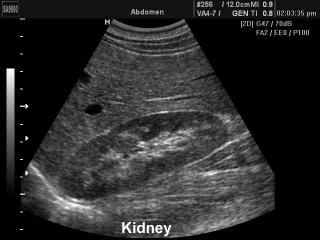

Kidney, B-mode

SonoAce-9900. Kidney, B-mode.